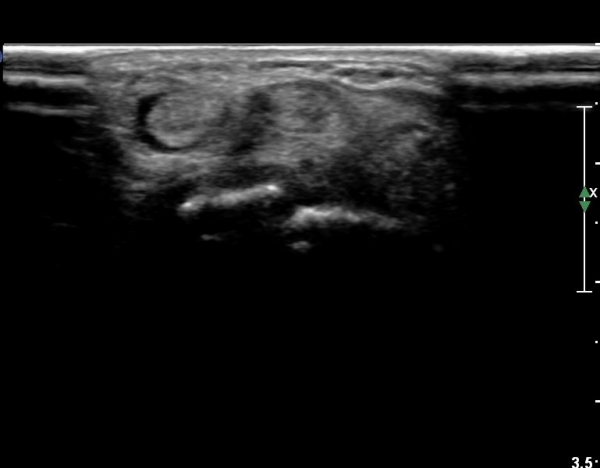

¿ä°ñ ¸»´Ü lister's tubercle ºÎÀ§¿¡¼­ Àå, ´Ü¿äÃø¼ö±Ù½ÅÀü°Ç Ⱦ´Ü¸é°Ë»ç¿¡¼­ ƯÀÌ ¼Ò°ßÀ» º¸ÀÌÁö

¾Ê´Â´Ù(»çÁø 3).